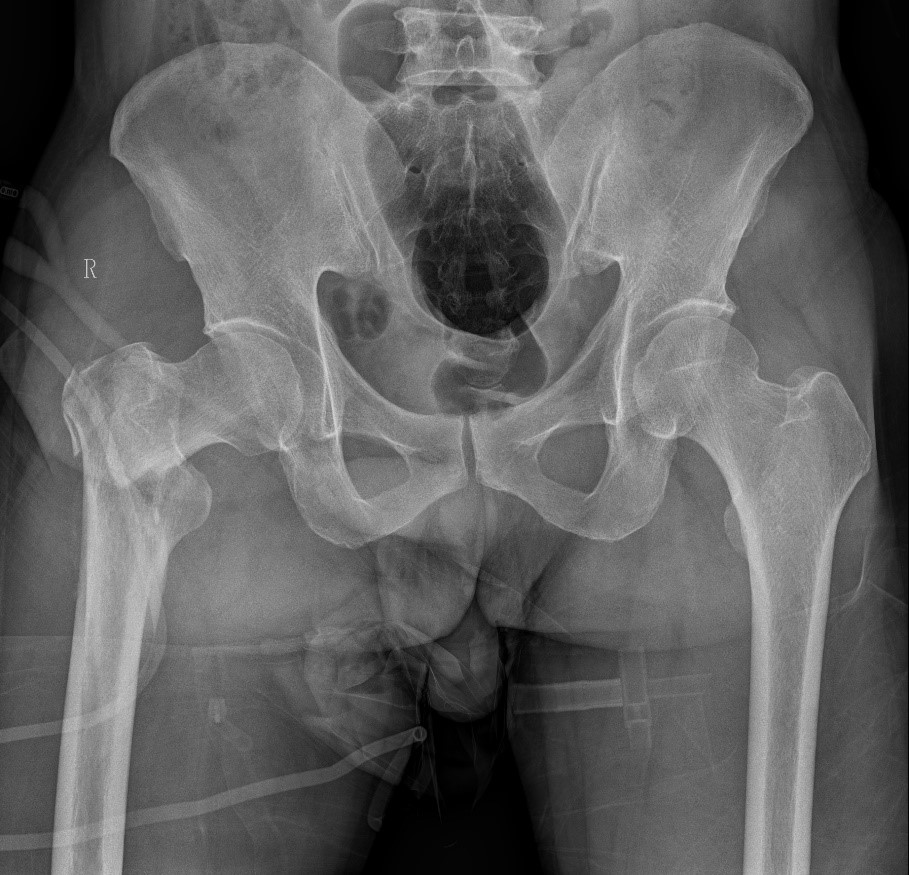

患者情况:吴先生因路面湿滑不慎摔倒,导致右髋部疼痛并活动受限,经检查确诊为股骨粗隆间骨折。

1.骨折部位解剖重建的准确性;

2.内固定材料的选择及固定强度的保障。